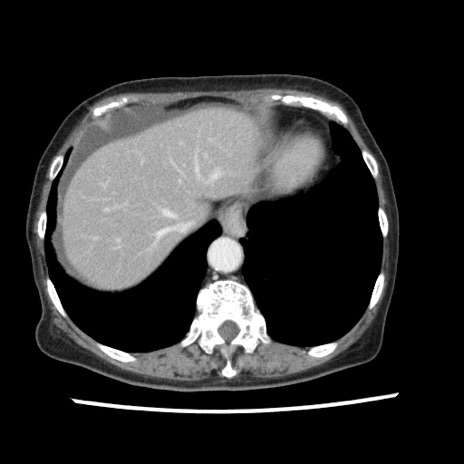

冠状断像

【症例】80歳代女性

【主訴】腹痛

【現病歴】8時間前から腹痛あり来院。

【既往歴】糖尿病、脂質異常症、子宮体癌にて子宮全摘術

【身体所見】意識清明・会話良好だが腹痛で苦悶様、全腹部にわたって反跳痛と圧痛あり

【データ】WBC 13600、CRP 0.14、LDH 224、CK 90